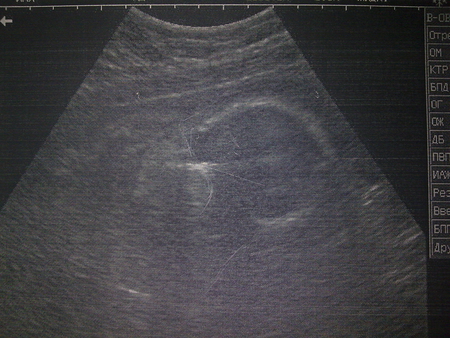

92 24 месяца

Как видно из таблицы, самый маленький размер соответствует росту ребенка 56 сантиметров. Вещей этого размера должно быть немного, так как они быстро становятся малы. В среднем, малыши рождаются длиной 51-53 сантиметра, но сейчас отмечается появление на свет крупных детей ростом 55-57 сантиметров. Поэтому, если УЗИ показывается, что вы носите богатыря, то, возможно, следует покапать первую одежду, начиная с 62 размера.